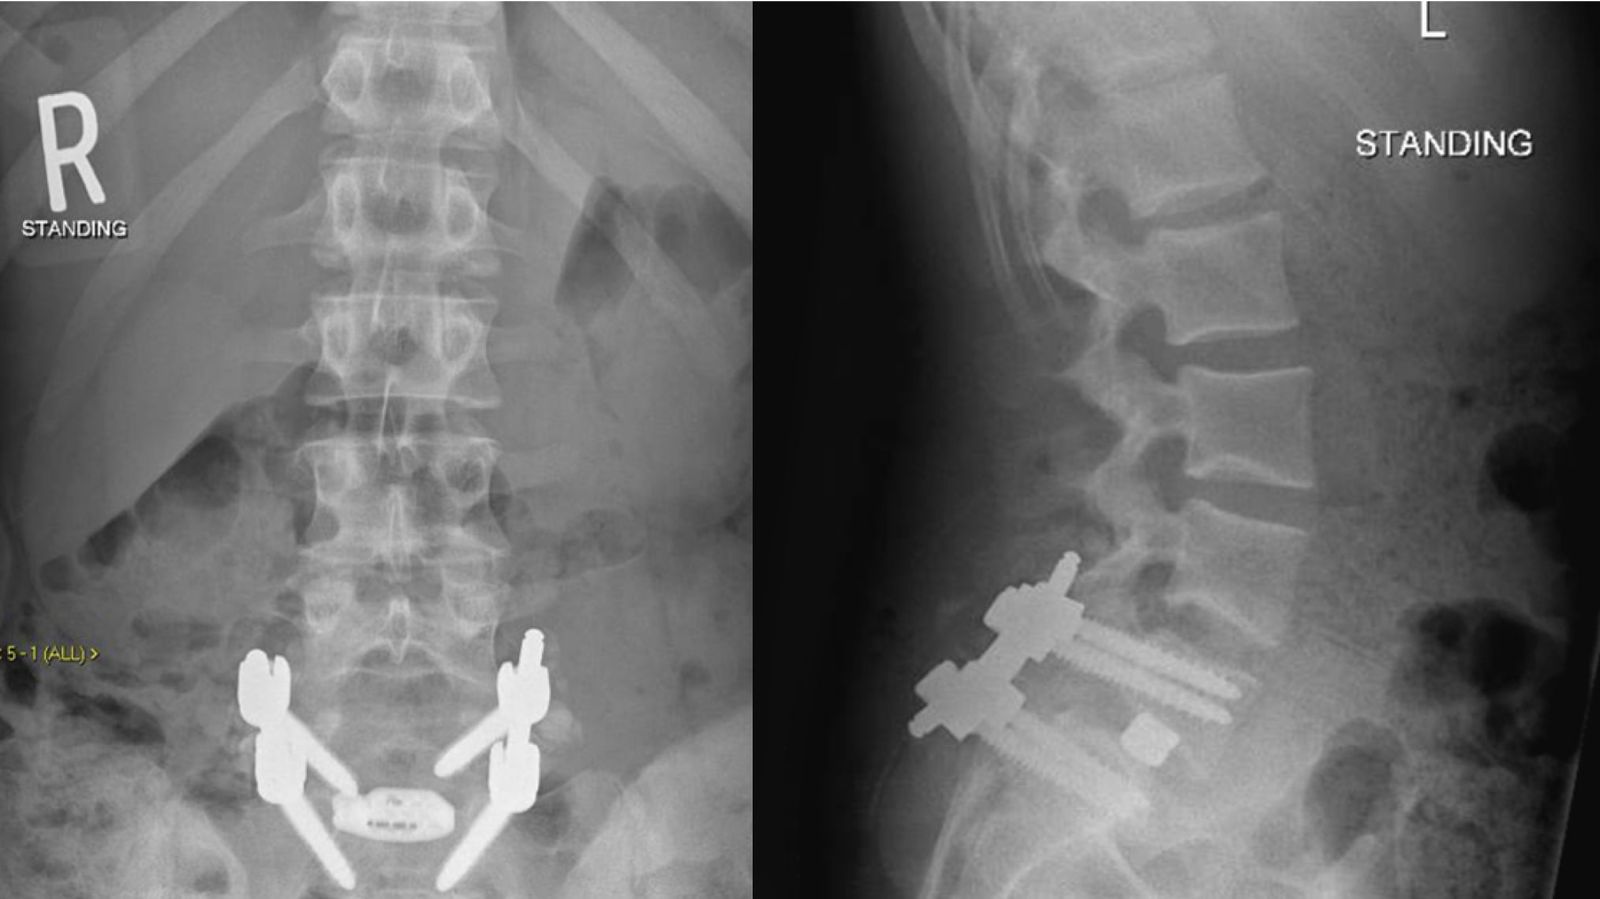

TLIF

TLIF stands for Transforaminal Lumbar Interbody Fusion, a type of spinal fusion surgery.

This is one method of performing lumbar interbody fusion, wherein the degenerated disc is removed, and the space fused together with a bone graft/cage.

The disc is removed completely, leaving only the bone edge of the vertebral body (end plates). The space created is filled with bone graft and/or a cage and placed between the outer segment of the spine between the transverse process (inter-transverse region). The patient’s own bone will gradually grow into the bone graft over time.

Screws and rods are fixed to stabilise the spine.